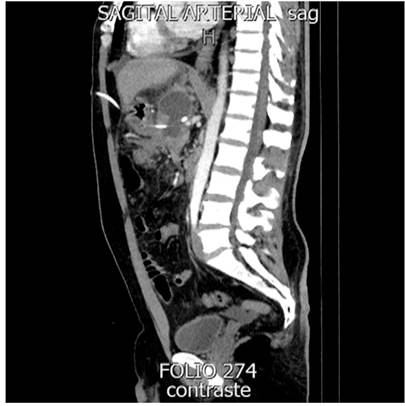

En relación con las características de los pacientes, 5 eran hombres con media de edad de 39 años. Todos los pacientes presentaron NPI como indicación inicial para el drenaje percutáneo. Los abordajes percutáneos para el tratamiento de la NPI fueron el transgástrico, transperitoneal y transretroperitoneal guiado por imágenes, combinándolos dependiendo cada caso clínico (Figura 1 y 2, Tabla 1).

Se utilizaron catéteres multipropósito pigtail, entre 10 y 12 Fr. El tiempo promedio de resolución de la NPI fue de 42 días.

En cuanto al diagnóstico de la DDP, 4 fueron mediante tomografía axial computarizada (TAC) y 2 por resonancia magnética (RM). Como resultado, se obtuvieron 4 (66,6 %) DDP parciales y 2 (33,4 %) totales. Todas las DDP se ubicaron en el cuerpo del páncreas.